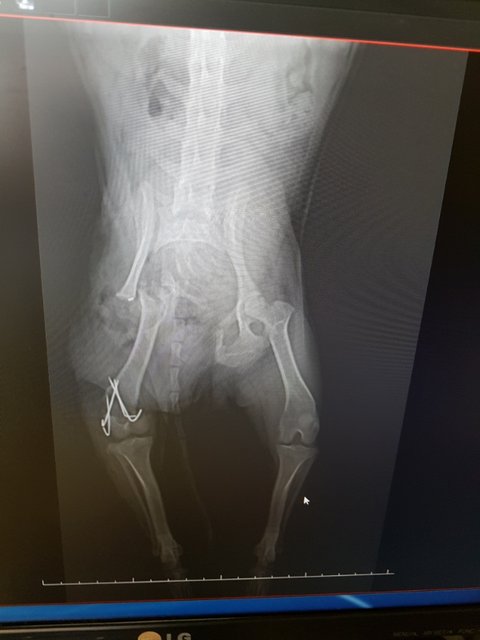

#김제보호소 #뒷다리골반복합골절 #수술했습니다 #사상충치료해야합니다.

골반은 플레이트를 지지해줄 지지대가 없어 어긋난 골반뼈만 잘라주고 자리를 잡아주셨다고 합니다

다리는 뼈가 어긋나 붙고있어 어긋난 부분을 바로잡고 부러진부분엔 플레이트를 되어 고정했다고 합니다